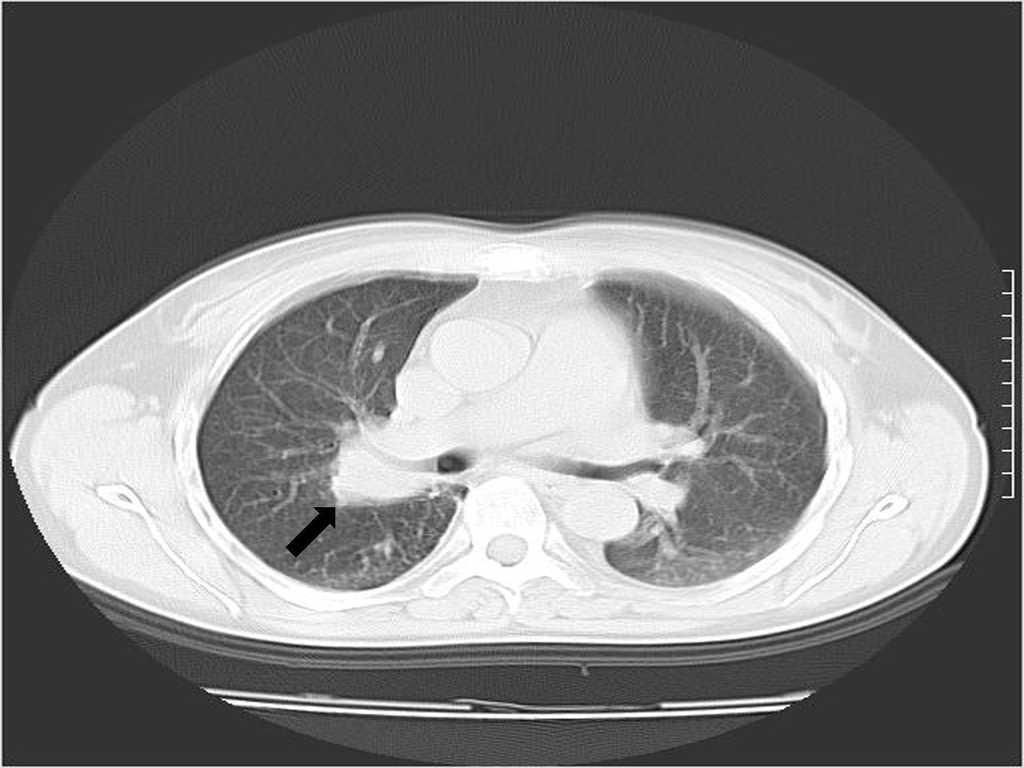

Mujer de 38 años, con trasplante renal de donante cadáver normofuncionante desde hace 3 años, tratada con prednisona, azatioprina y ciclosporina, que ingresa en nuestro servicio con cuadro de neumonía de lenta resolución y creatinina sérica de 0,9 mg/dl. En la radiografía de tórax se constata una imagen nodular en el hilio pulmonar derecho (figura 1). Se solicita una TC (figura 2) en la que se comprueba una masa sólida en el bronquio segmentario superior derecho asociada con lesiones inflamatorias del parénquima. Se realiza fibrobroncoscopia, observándose una tumoración que hace relieve endobronquial con elementos inflamatorios en su superficie. Se toma biopsia que se envía al Hospital Hermanos Ameijeiras, donde se emite el diagnóstico patológico de un seudotumor inflamatorio por Rhodococcus equi ante el hallazgo de reacción inflamatoria y la comprobación de cocos intramacrófagos, así como cuerpos de Michaelis-Gutman. Esta paciente recibió tratamiento prolongado (60 días) con meropenem y ciprofloxacino, y la imagen tumoral había desaparecido en la tomografía axial computarizada evolutiva realizada tres meses más tarde.

Figura 1. Imagen que muestra engrosamiento del hilio pulmonar derecho.